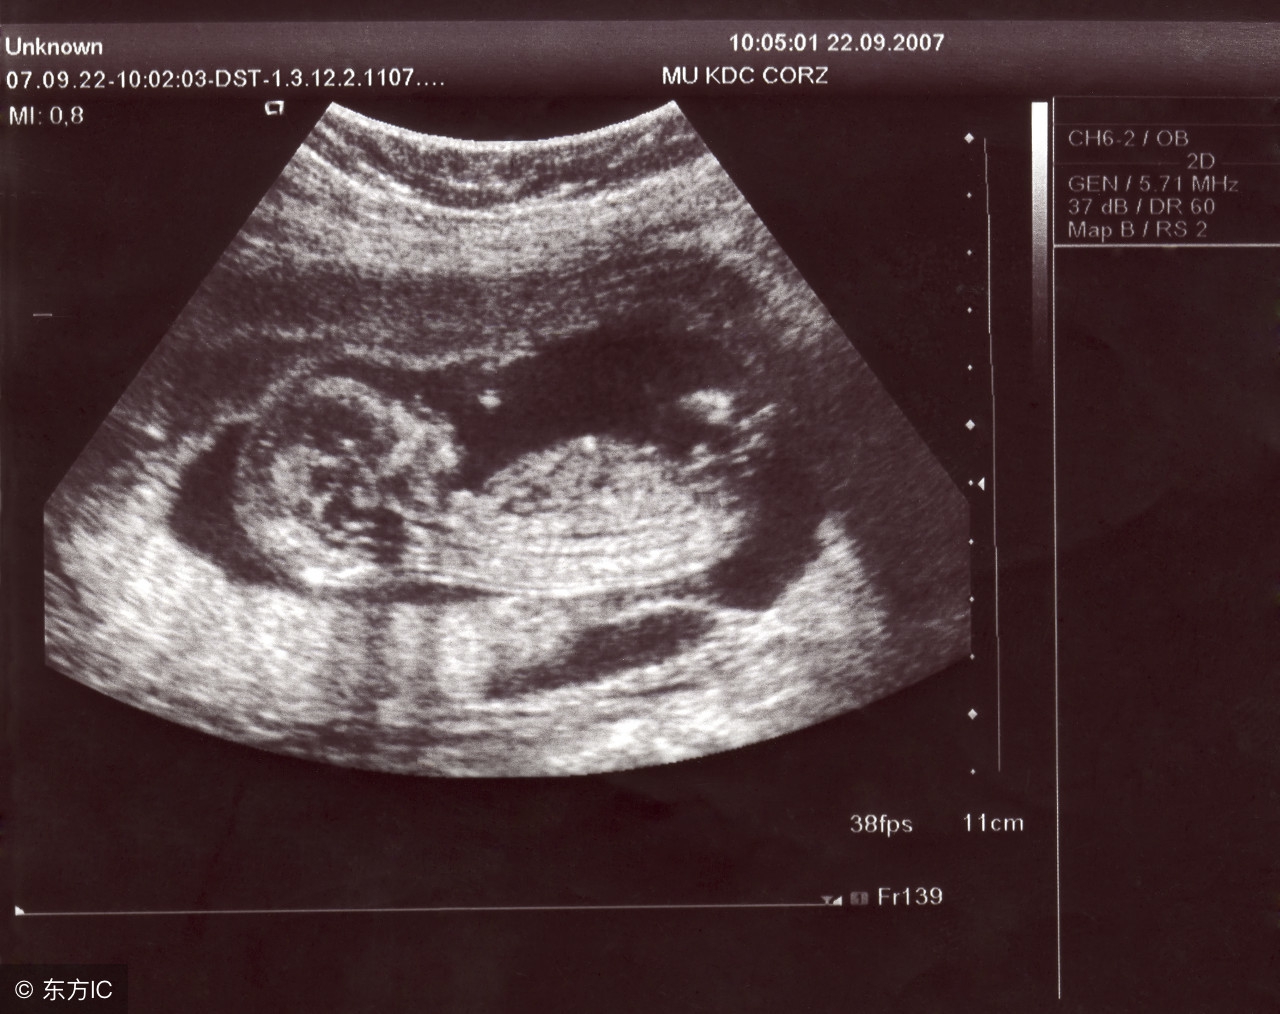

若是在怀孕6~7周时超声检查仍不见胎心出现,就要怀疑是否是“萎缩性胚囊”。因为,自然因素而导致流产的几率高达15%~20%。胚胎萎缩有60%左右是因为受精卵染色体异常,或受精卵本身有问题所致,因此,这并不是由准爸爸准妈妈的粗心大意造成,而是自然淘汰的结果。遇到此类情况,父母双方首先应做坦然接受,并配合医师做适当处理,才是应该有的正确态度。